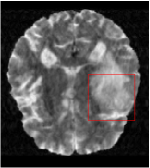

Qualitative comparison between conventional and Meta-learning methods are shown in Figure 1 and 3, which display the reconstructed MR images of the same slice for T1 and T2 respectively, we label the zoomed-in details of HGG in the red boxes. We observe the evidence that conventional learning is more blurry and lost sharp edges, especially in lower CS ratios. From the point-wise error map, we find meta-learning has the ability to reduce noises especially in some detailed and complicated regions comparing to conventional learning.

In this section, we test the generalizability of the proposed model that tests on unseen tasks. We fix the well-trained task-invariant parameter and only train for sampling ratios 15%, 25% and 35% with radio masks and sampling ratios 10%, 20%, 30% and 40% with Cartesian masks. In this experiment, we only used 100 training data for each CS ratio and apply a total of 50 epochs. The averaged evaluation values and standard deviations are listed in Table 5.4 and 5.4 for reconstructed T1 and T2 brain images respectively that proceed with radio masks, and Table 5.4 shows the qualitative performance for reconstructed T2 brain image that applied random Cartesian sampling masks. In T1 image reconstruction results, meta-learning improved 1.6921 dB in PSNR for 15% CS ratio, 1.6608 dB for 25% CS ratio, and 0.5764 dB for 35% comparing to the conventional method, which in the tendency that the level of reconstruction quality for lower CS ratios improved more than higher CS ratios. A similar trend happens in T2 reconstruction results with different sampling masks. The qualitative comparisons are illustrated in Figure 2, 4 and 5 for T1 and T2 images tested in skewed CS ratios in radio masks, and T2 images tested in Cartesian masks with regular CS ratios respectively. In the experiments that conducted with radio masks, meta-learning is superior to conventional learning especially at CS ratio 15%, one can observe that the detailed region in red boxes keeps edges and is more close to the true image, while conventional method reconstructions are hazier and lost details in some complicated tissue. The point-wise error map also indicates that Meta-learning has the ability to suppress noises.